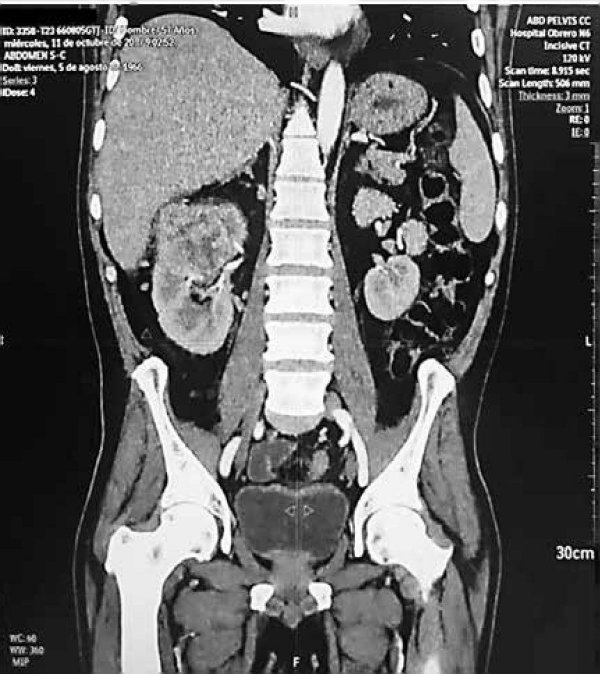

Tomografía axial computada no contrastada (TAC): Muestra imagen de tumoración renal derecha dependiente de polo superior (FIGURA 2).

FIGURA 2: TAC con corte coronal se observa lesión tumoral en polo superior de riñón derecho